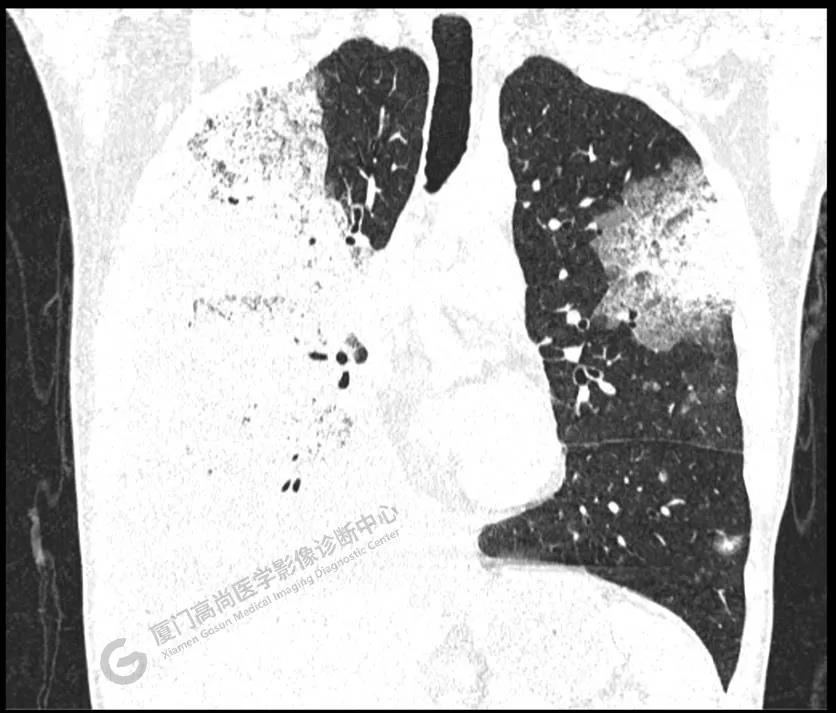

PET/CT所見:雙肺大片實(shí)變影及磨玻璃影,部分呈地圖樣改變,累及右肺尖,部分放射性攝取輕微增高,SUVmax 1.77,其內(nèi)見多發(fā)支氣管充氣征象。

影像診斷: 雙肺大片實(shí)變影及磨玻璃影,大部分代謝不高,局部代謝輕微增高,考慮肺泡蛋白沉積癥,建議病理學(xué)檢查或肺泡灌洗物檢查。

影像學(xué)表現(xiàn):HRCT上雙肺斑片影,以肺門為中心呈蝶翼狀對稱分布;病變可隨機(jī)分布在中央?yún)^(qū)、周圍區(qū)或全肺葉,病灶與正常分組織分界清楚,呈典型“地圖樣”改變;有支氣管充氣征,但表現(xiàn)為充氣支氣管細(xì)小且數(shù)量及分布稀少;“碎石路”征由彌漫性磨玻璃影及內(nèi)部網(wǎng)格樣小葉間隔增厚組成(鋪路石樣表現(xiàn))。無空洞、蜂窩狀改變、淋巴結(jié)腫大、胸腔積液及明顯實(shí)變等。肺內(nèi)病灶累及范圍、磨玻璃密度高低與PAP患者的病情嚴(yán)重程度相關(guān),嚴(yán)重者病灶累及全肺,同時出現(xiàn)肺內(nèi)大片實(shí)變,并見充氣支氣管征象。PAP影像學(xué)表現(xiàn)程度與臨床癥狀、體征嚴(yán)重程度不成比例,表現(xiàn)為影像改變重,臨床癥狀輕。